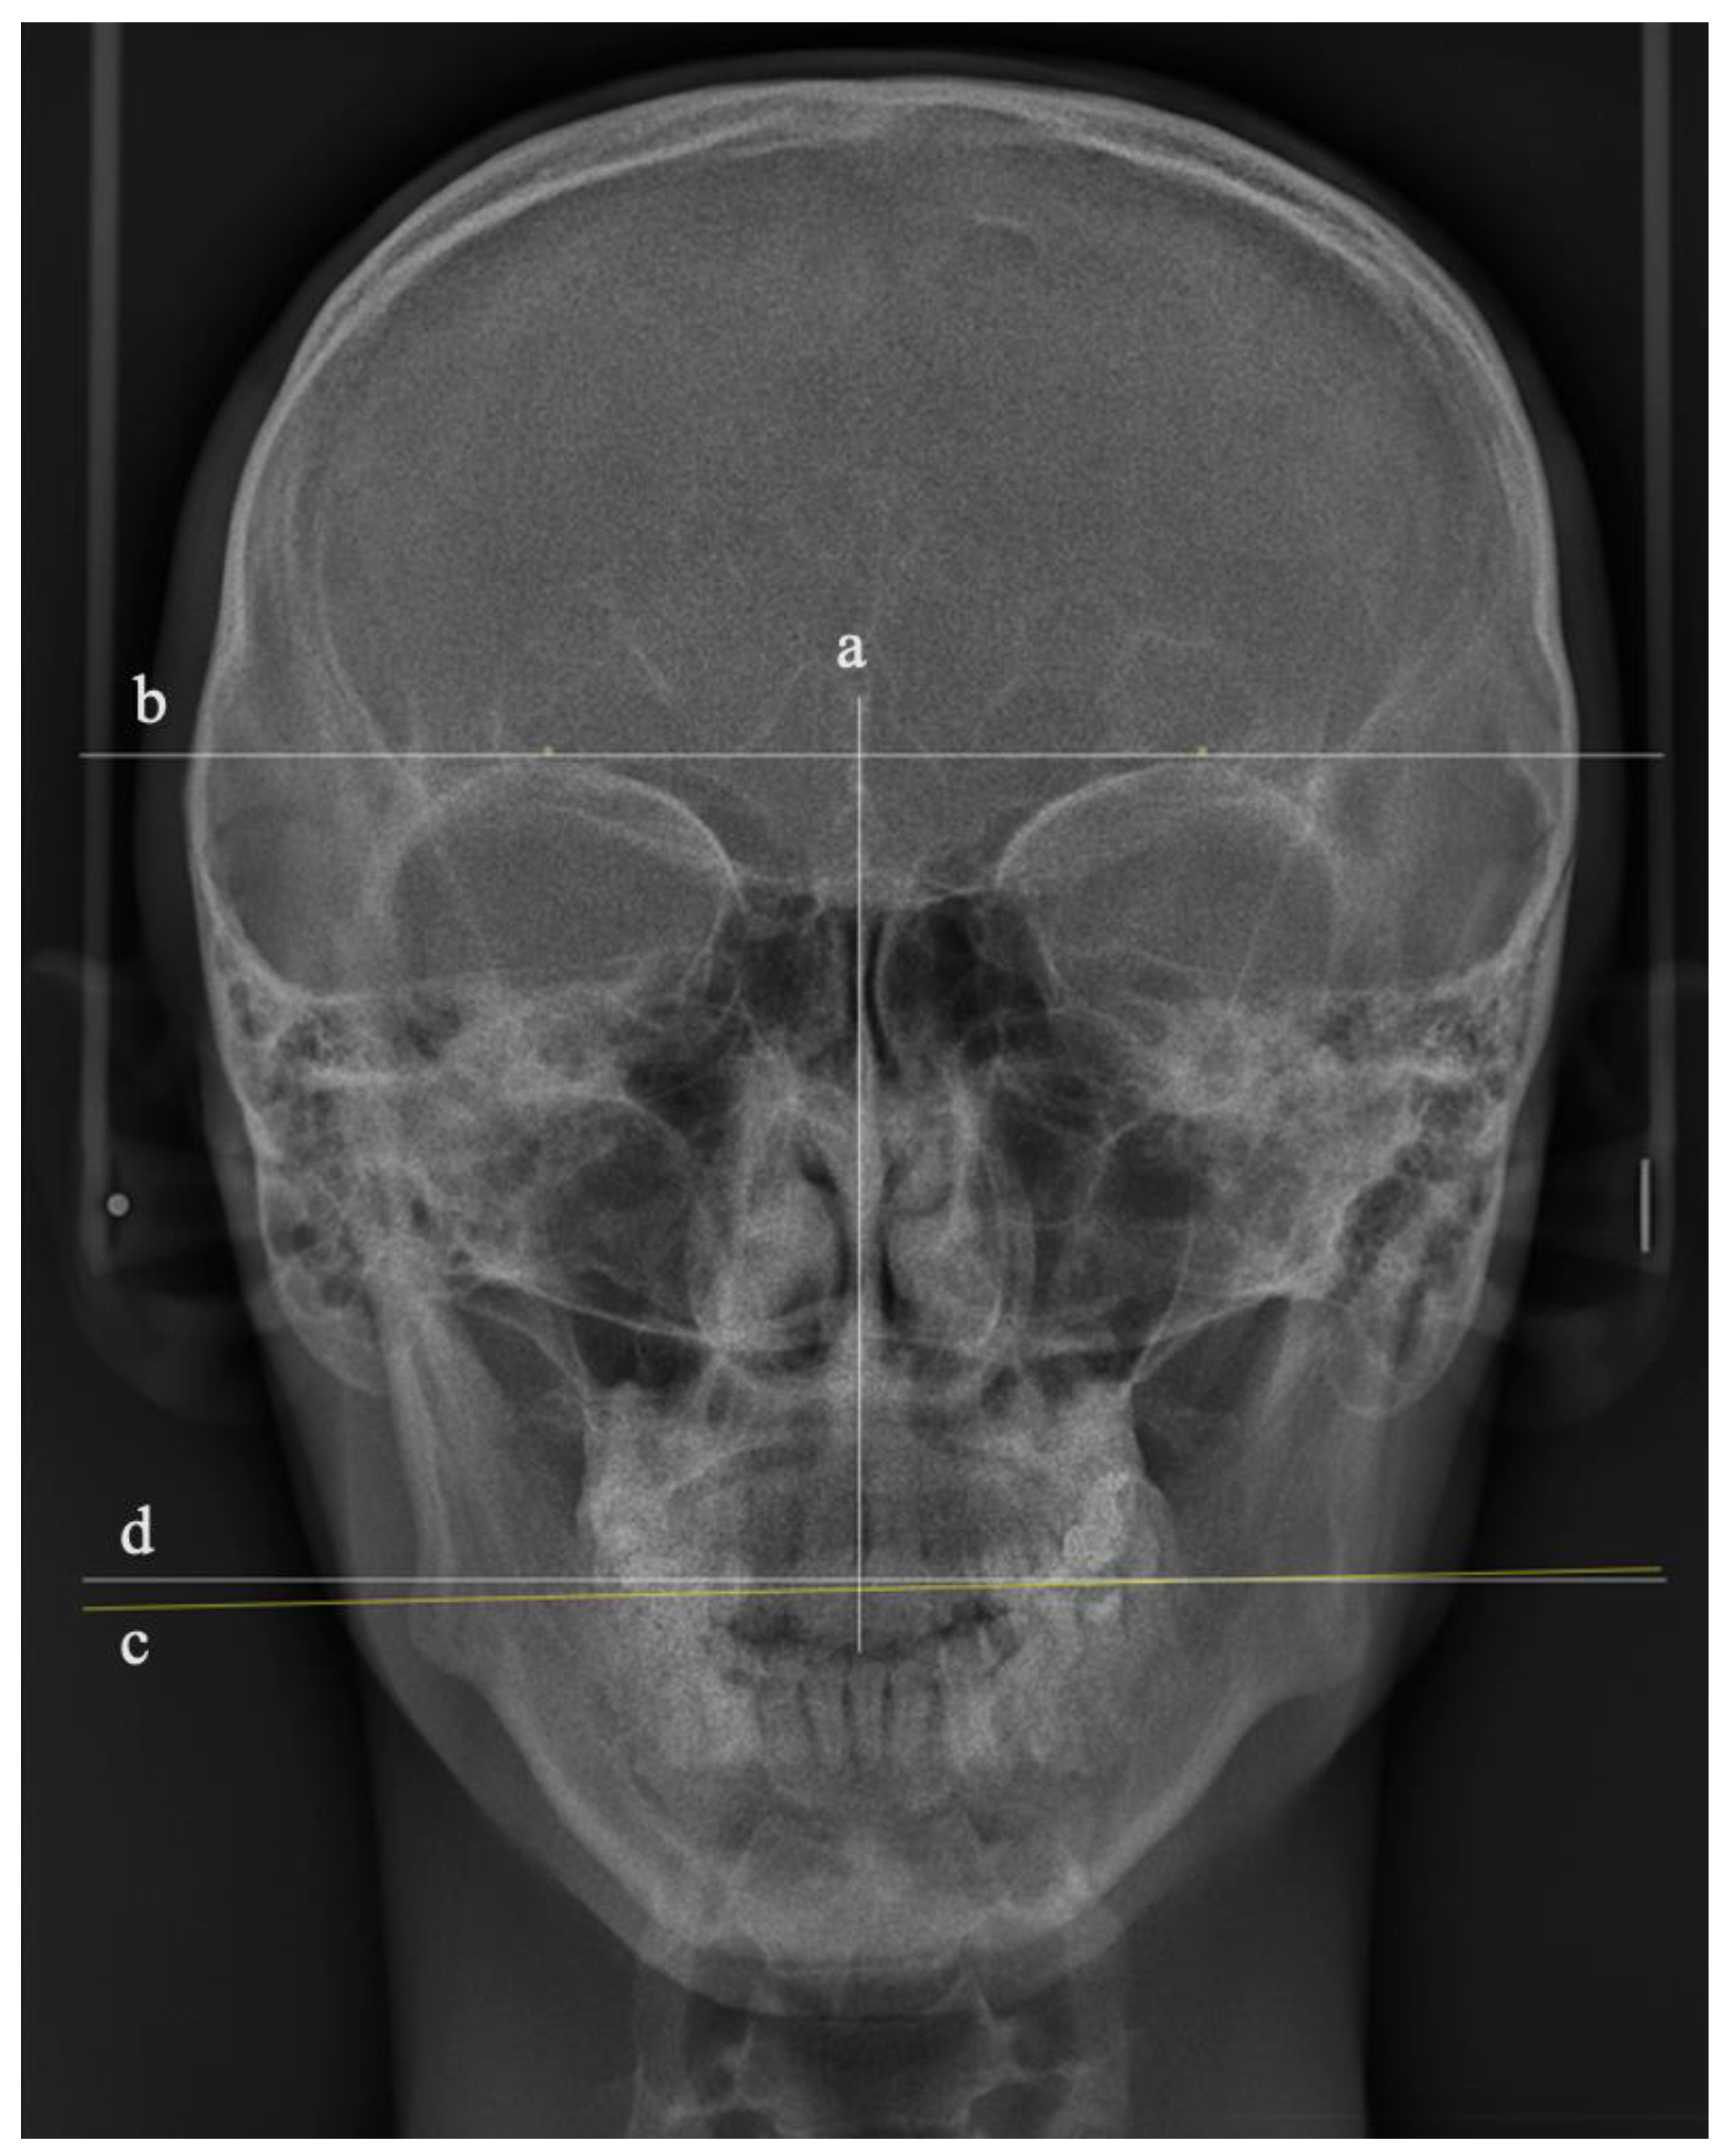

The manipulated 36 PA images were printed and traced by a single author. To measure the OC cephalometrically, three lines were drawn using a fine-tip pen (0.20 mm) (Sakura Pigman micron pen, Osaka, Japan), as shown in Figure 2:

• A vertical line represents the facial midline, drawn from the crista galli to a point in the upper third of the nasal septum;

• A line represents the true horizontal plane, drawn as a tangent passing through the supra-orbital rims perpendicular to the vertical line;

• A line represents the occlusal plane (OP), drawn as a tangent to the most convex point of the buccal surfaces of the upper right and left first molars.

The degree of OC was represented by the angle bisecting these two horizontal lines [16]. Considering the distance between the two horizontal lines, an additional line parallel to the true horizontal tangent was drawn closer to the OP tangent to measure the OC angle (Figure 2). To assess the accuracy of the tracing, the angle of OC in degrees for all the traced 36 PA cephalometric images was remeasured by a second researcher. The set of 36 PA cephalometric images was arranged randomly to reduce systematic measurement errors among the participants, enhancing the study’s internal validity.

Figure 2. Illustration of the tracing lines of the PA cephalometric images: (a) vertical line representing the facial midline, (b) true horizontal line, (c) occlusal plane line, and (d) tangent parallel to the true horizontal line.